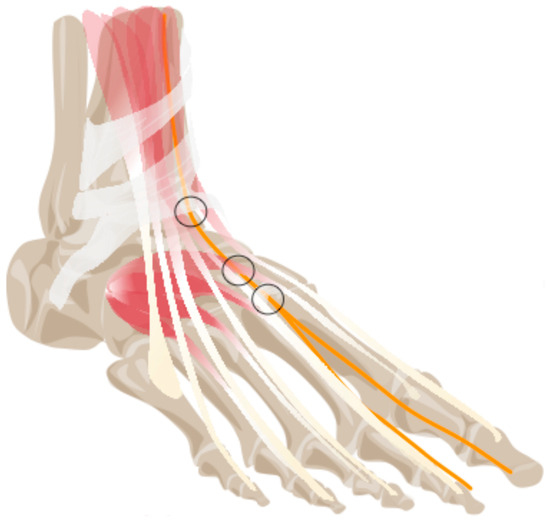

Thickening of Dorsal Foot Nerves: A Frequent Sonographic Finding in Asymptomatic Volunteers, Potentially Leading to False Positive Results

Objectives: Compression neuropathies such as Anterior Tarsal Tunnel Syndrome are usually associated with focal thickening at the compression site. This study aimed to determine the frequency and location of thickenings of dorsal foot nerves in asymptomatic, healthy volunteers. We hypothesized that focal nerve thickening of dorsal foot nerves is a frequent finding in asymptomatic individuals and occurs at anatomically plausible locations, potentially limiting the specificity of ultrasound in the diagnosis of anterior tarsal tunnel syndrome. Materials and Methods: In this prospective study, the nerves at the dorsal foot were examined with ultrasound in 60 volunteers without clinical signs of neuropathy. Cross-sectional area (CSA) changes along the nerve course were assessed, their anatomical location recorded, and demographic data collected. Results: Focal deep peroneal nerve (DPN) thickening was observed in 45% of participants, with a median CSA of 2.14 mm2 (range: 0.84–5.16) and median length of 3.98 mm (range: 1.46–9.95). The most frequent site was the first tarsometatarsal joint (41%). Thickening occurred across all age groups. Superficial peroneal nerve (SPN) thickening was found in 13.3% of participants, primarily affecting the intermediate branch, with a median CSA of 1.82 mm2 and length of 3.02 mm. No thickening was observed in the sural nerve (SN). A strong correlation was found between CSA and length of DPN thickening (r = 0.67, p < 0.001). Conclusions: Asymptomatic, focal thickening of dorsal foot nerves, particularly the DPN, is a frequent sonographic finding in healthy volunteers. These findings highlight the potential for false-positive ultrasound results and the necessity of correlating imaging findings with clinical examination when evaluating for anterior tarsal tunnel syndrome and similar neuropathies. Full article

Show Figures

Figure 1